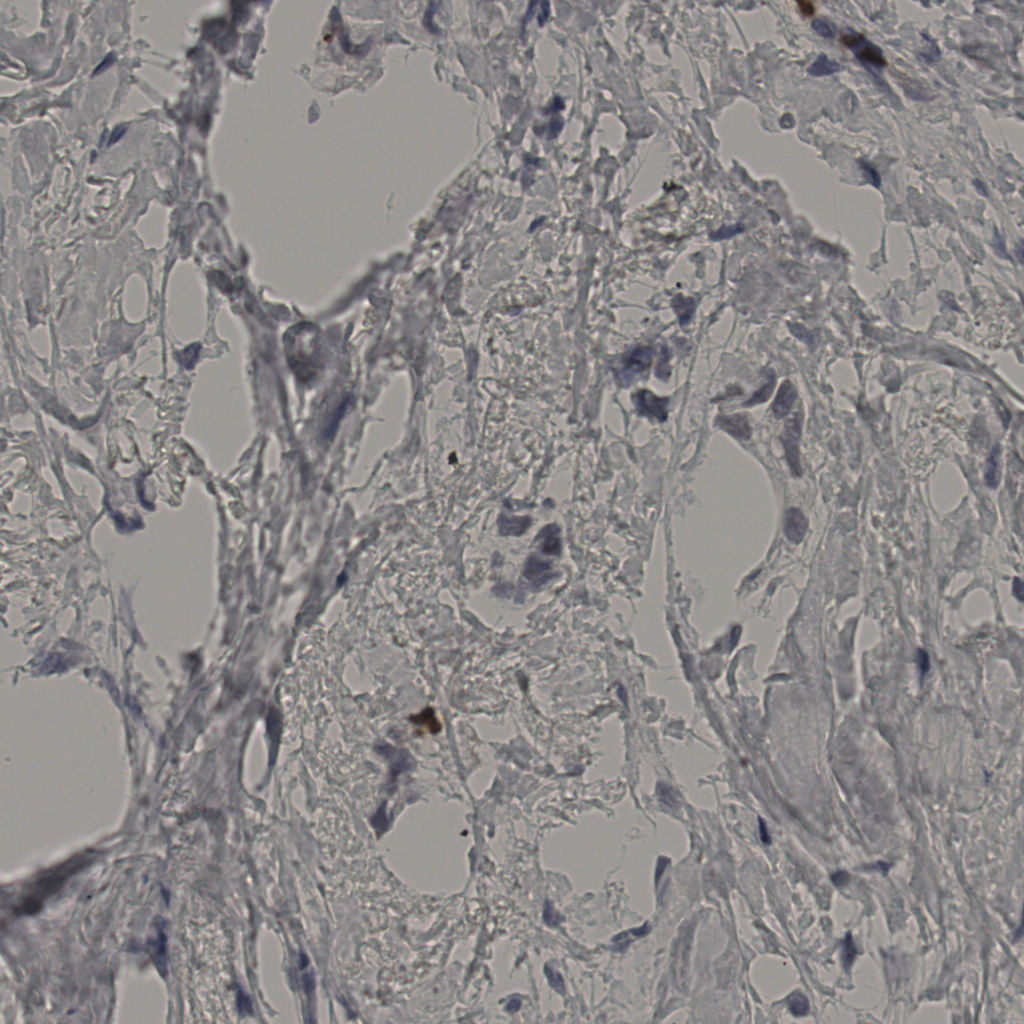

缩略图

标记后

标记前